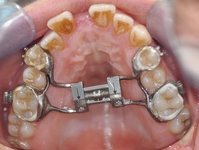

Dogo Çenesinin Gücü Ne Kadar Ton Basabiliyor?Dogo Argentino, güçlü yapısıyla dikkat çeken bir köpek ırkıdır. Bu ırk, av köpeği olarak yetiştirilmiş olup, kaslı yapısı ve güçlü çenesi ile bilinir. Dogo Argentino'nun çene gücü, hem avcılık yetenekleri hem de koruma işlevleri açısından oldukça önemlidir. Bu makalede, Dogo'nun çene gücünü detaylı bir şekilde inceleyeceğiz. Dogo Argentino'nun Çene AnatomisiDogo Argentino, güçlü bir çene yapısına sahip olmasıyla birlikte, bu güçlü yapı birkaç anatomik özellikten kaynaklanmaktadır: